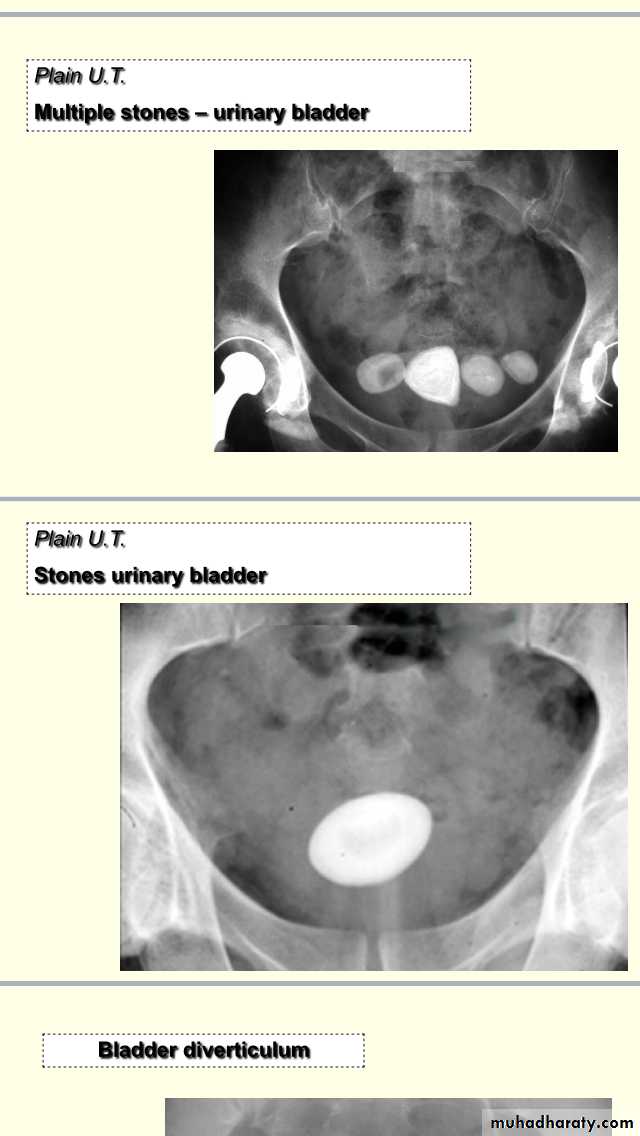

Uroradiology & Slides 1